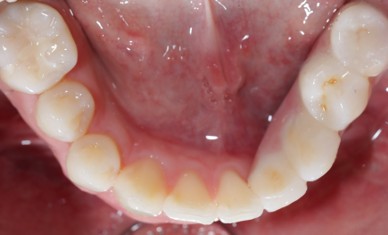

Prosthodontics (also known as dental prosthetics or prosthetic dentistry) is one of the nine dental specialties recognized by the American Dental Association (ADA). Prosthodontists specialize in the diagnosis, restoration, and replacement of missing teeth.

Extensive training and experience give prosthodontists a unique understanding of restoring the dynamics of a smile and healthy mouth with the creation of tooth prostheses. Becoming a prosthodontist requires an additional three years of specialty training after obtaining a DMD (Doctor of Dental Medicine) or DDS (Doctor of Dental Surgery) degree.